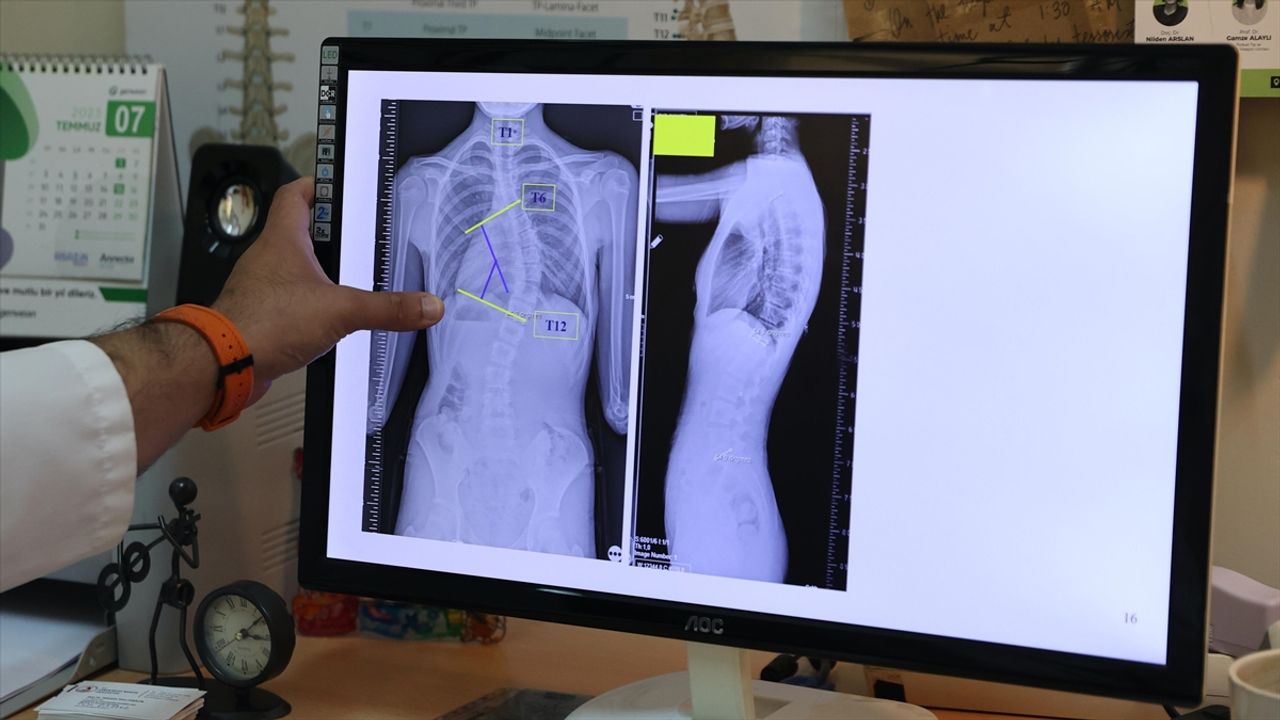

Başaran, yaptığı yazılı açıklamada, skolyozun omurganın üç boyutlu düzlemde sağa ya da sola eğrilmesi anlamına geldiğini, omurgada S veya C şeklindeki bu eğilmelerin yüzde 80'inin nedeninin bilinmediğini aktardı.

"Toplumda 10 dereceye kadar olan omurga eğriliklerine çok sık rastlıyoruz. Bunları normal, postürel eğrilikler olarak tanımlıyoruz. 10 dereceyi geçen eğriliklerde skolyoz hastalığı tanısı koyuyoruz. 20 dereceye kadar olan eğrilikleri 6 aylık aralıklarla büyüme dönemlerine göre takip ediyoruz. 20 dereceyi geçen eğriliklerde ise çocukları egzersiz programına alıyoruz ya da çeşitli korselerle hastalığının ilerlemesini engellemeye çalışıyoruz."

Çocukların hızlı büyüdüğü dönemde önerdikleri korse ve egzersizin, aslında skolyozu iyileştirmeye yönelik tedaviler olmadığını, burada cerrahi sınıra yaklaşmadan hastalığı durdurabilmeyi amaçladıklarını ifade eden Başaran, erişkinlik döneminde 40 dereceyi aşan omurga eğriliğinde cerrahi tedavi önerdiklerini aktardı.